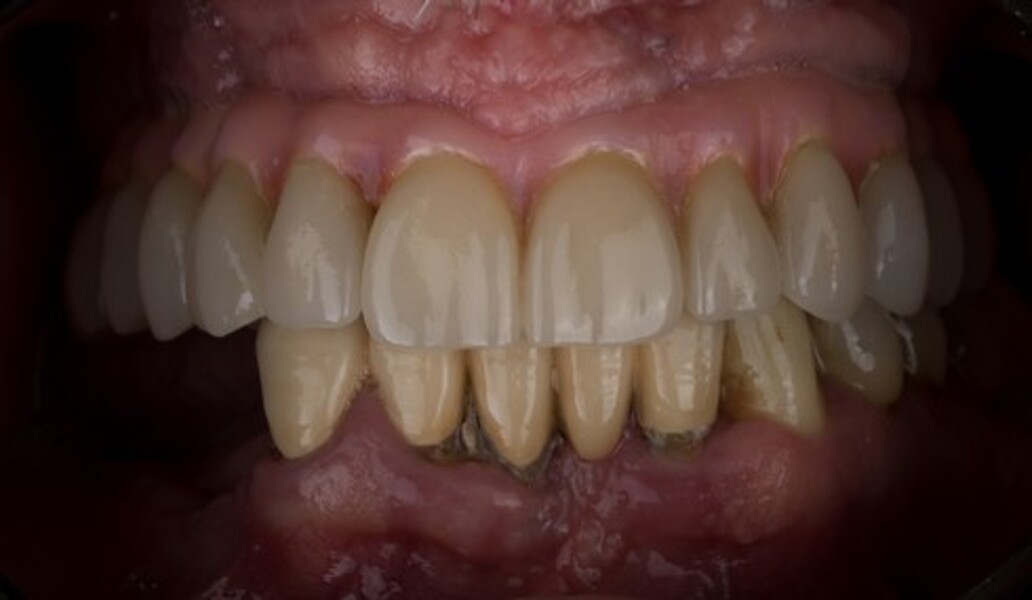

MAGICAL All on FOUR